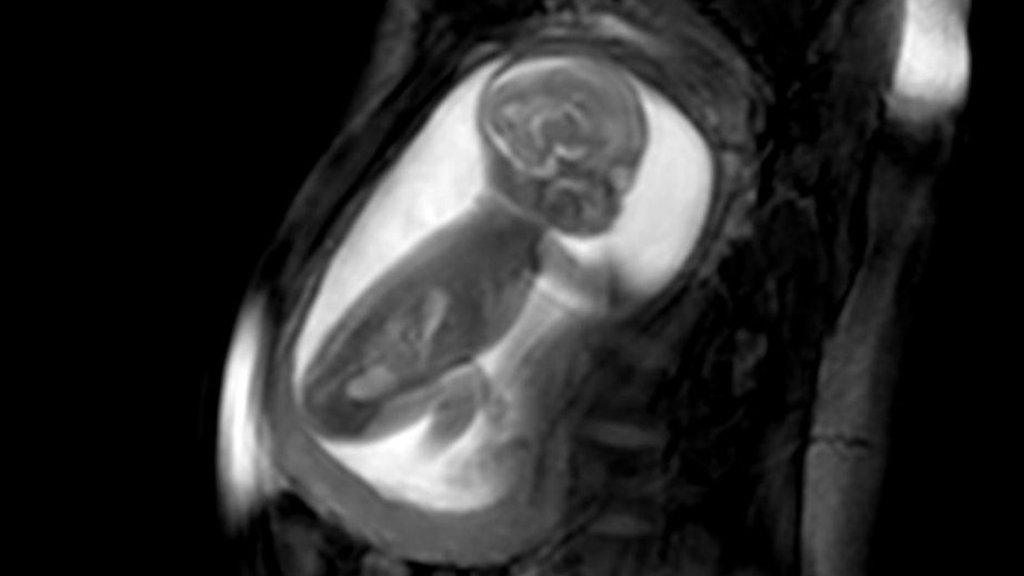

Southampton Children's Hospital has created more than 100 exact replicas from medical scans since 2019, enabling surgeons to practise procedures in advance.

Belfast manufacturer Axial3D has worked with University Hospital Southampton NHS Foundation Trust to evolve the technology, replacing early rigid models with soft ones that can be cut and stitched.